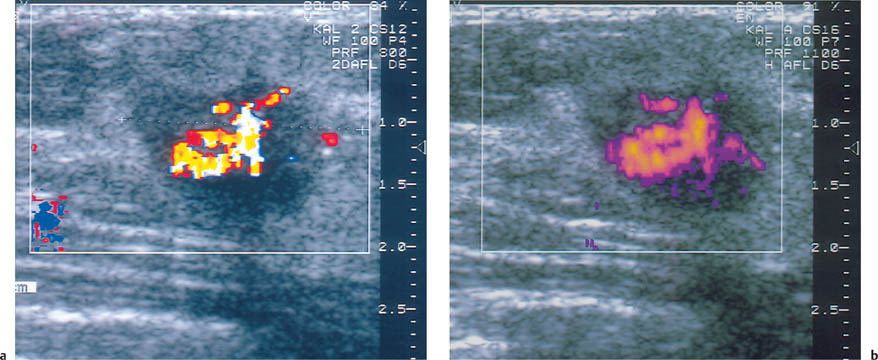

19 Doppler Ultrasound The vascularization of malignant tumors is a phenomenon well known from pathologic, biochemical, and angiographic studies, and we know that the degree of neovascularization correlates with the biologic behavior of the tumor. Thermography, once widely used as an adjunct to clinical examination, can detect the change in surface temperature associated with the focal increase in blood flow to a breast malignancy. However, it has been discredited as a screening method for breast cancer because of its low sensitivity, poor specificity (inflammatory processes as well as cancer are associated with local heat), and lack of precise anatomic localization (Williams et al., 1990). Contrast-enhanced MRI is also based on angiogenesis in malignant tumors as well as other factors such as membrane permeability. For many cancers, but certainly not all, there is an intense rapid rise followed by signal washout after the administration of a paramagnetic contrast agent, most commonly a gadolinium chelate such as gadopentate dimeglumine. The measurement of tumor blood flow is more applicable to lesion characterization than to screening. But there are anatomic situations that hamper evaluation of the breast tissue, and there are tumors that do not display typical diagnostic features, and the measurement of tissue blood flow can be helpful in evaluating problem cases of this kind. It should be understood, however, that the measurement of tumor blood flow is a nonspecific assessment that cannot differentiate lesions with absolute confidence. The degree of blood flow correlates with tissue metabolism. Thus, while fast-growing malignancies generally have a copious blood supply, blood flow is also increased in proliferative benign tumors, in pregnancy and lactation, and in inflammatory conditions. Doppler ultrasound has been used for more than 20 years to analyze blood flow in breast tumors. Initially only continuous-wave (CW) Doppler systems were available. These devices are very sensitive, but they require an experienced user and it is difficult to examine nonpalpable lesions. Pulsed Doppler systems became popular in the early 1980 s, as they allow for selective flow sampling in vessels that are located by ultrasound imaging. Tumor vessels are very small, however, and usually cannot be visualized in the B-mode image. It is tedious to move the Doppler sample volume through the image while searching the tumor and its surroundings for blood vessels. Also, most of the older duplex scanners used a low frequency and were relatively insensitive in detecting tumor vessels. As a result, duplex scanning did not find significant applications in tumor diagnosis. Color flow imaging paved the way for the use of Doppler ultra-sound in tumor diagnosis. The first instruments had poor sensitivity. By the 1990 s, however, color Doppler technology had advanced sufficiently to permit the effective localization of tumor vessels (Fig. 19.1). This was achieved through the use of higher Doppler frequencies and improved signal processing. The recording of Doppler spectra was also improved and provides additional information on tumor blood flow (Fig. 19.2). Nevertheless, color Doppler demonstrates only a portion of the vessels. This is due to the limited sensitivity of Doppler in detecting microscopically small vessels and the dependence of the Doppler principle on the beam–vessel angle. Vessels that are perpendicular to the beam direction are poorly detected. Blood flowing in the direction of the beam results in a higher frequency shift and a better recorded signal. Fig. 19.1 Color Doppler image of invasive ductal carcinoma. The greatest vascular density is found at the periphery of the tumor. Note the predominantly radial pattern of vessels converging on the tumor. The high sensitivity setting, with a PRF of 800 Hz, often leads to aliasing in the vessels due to the high flow velocities. This must be tolerated, since increasing the PRF would decrease Doppler sensitivity and reduce the number of detectable vessels. Fig. 19.2 Color Doppler and duplex sonography for the measurement of blood flow. Again, most vessels are found at the tumor periphery. The Doppler spectrum shows a high systolic blood flow velocity (37.9 cm/s) and an absence of flow in diastole (RI = 1.0). This high resistance pattern is typical of breast carcinoma. Breast carcinomas often have a firm consistency, exerting a pressure that collapses the blood vessels within the tumor. As a result, only peripheral vessels can be seen in most cases and the flow resistance is high. To improve the visualization of small vessels and avoid the problem of insonation angle, a different method of signal processing was developed. This technique, called power Doppler, does not register the angle-dependent frequency shift but the intensity (amplitude) of the reflected signals, which depends on volume flow. As a result, the course of tumor vessels is more clearly visualized (Fig. 19.3 a, b). This technique is susceptible to artifacts, however, and much experience is needed to interpret the images correctly. Another disadvantage is that, for the present, power Doppler imaging yields nonquantitative information. The image is interpreted subjectively, and there are no objective parameters that can be used for tumor differentiation. For these reasons, color Doppler is still preferred. It is easily combined with duplex technology for concomitant flow imaging and flowmetry. However, this requires a sensitive instrument with optimum settings. Given the range of variation among different instruments, standardization is difficult to achieve. In our previous studies at the University of Freiburg, we used the ATL UM9 HDI (Philips Medical Systems, Bothell, WA) color flow imager with a 10–5-MHz linear-array transducer. We used a 50–100 Hz filter and a pulse repetition frequency (PRF) of 800–1000 Hz. The power and gain were set as high as possible, that is, just below the noise level. Doppler ultrasound is used to investigate focal abnormalities rather than to scan the entire breast. Given the variability of tumor blood flow, all vessels should be sampled for the quantitation of flow. Because vessels often are not visualized within malignant tumors, particular attention should be given to feeding vessels that enter the periphery of the mass. With just enough pressure to maintain contact, the transducer should be placed lightly on the breast to avoid vascular compression. Before any vessels are sampled, various insonation angles should be tested to obtain an optimum Doppler signal. First a slow scan through the tumor is done in the color Doppler mode so that all the vessels can be located and counted. Then the examination is completed by analyzing flow signals in the duplex mode. Usually the course of the vessels can be seen, and so the probe angle can be adjusted to ensure an accurate measurement of flow velocity. Duplex analysis should include the determination of maximum systolic velocity (S) and end-diastolic velocity (D). This provides information on total blood flow and makes it possible to calculate indices from the Doppler spectra. The most important index to be determined is usually the resistance index (RI) or the AB ratio: RI = (S – D)/S AB ratio =S/D The pulsatility index (PI) is less frequently determined because it requires fitting an envelope curve to the Doppler spectrum. This is time-consuming and fraught with potential errors. Our comparative measurements have shown, moreover, that this index correlates closely with the RI and the AB ratio. Flow velocity analysis provides a basis for various calculations. For example, the vessel with the highest-velocity flow can be used for tumor differentiation. It is also possible to calculate the mean value for all the flow velocities measured in a particular tumor. Because carcinomas are supplied by many small, low-flow vessels in addition to a few large vessels, the mean velocity may be low despite a high total blood flow. A better way to assess total blood flow is to add together all the flow velocities measured in the tumor. It would be simpler and more accurate to use a computer to extract the total blood flow from the color Doppler data. Fig. 19.3 a, b Color Doppler and power Doppler images of a solid cellular carcinoma. The relatively soft consistency of this tumor accounts for the central vascular density. a Branching vessels can be identified in the color Doppler image. b The course of the vessel is seen somewhat more clearly in the power Doppler image, but individual vascular branches are not defined. Malignant tumors are associated with an increased number of blood vessels (Fig. 19.1, Table 19.1), which converge on the tumor and enter it in a radial pattern. Often, however, only vessels at the tumor periphery are visualized while vessels inside the tumor are collapsed as a result of the very firm consistency of most carcinomas. Although the vessels in malignancies often communicate through shunts and do not have a muscular coat, the hard tumor consistency leads to a high flow resistance (Fig. 19.2). Even so, the flow velocities in most tumor vessels are increased but are highly variable. The same applies to the Doppler spectra that are sampled from the vessels.